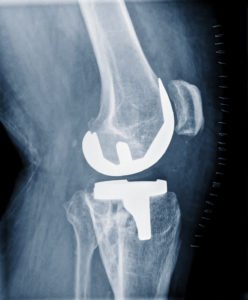

Knee Replacement Surgery

The knee is the largest joint in the body and as such, undergoes a lot of stress. Whether it’s from wear and tear, an injury, carrying too much weight or degenerative joint disease, there is a good chance you or someone you know will be one of the more than 500,000 people each year who undergo a knee replacement procedure. If your knees are starting to bear the brunt of the pain and aren’t what they used to be, your orthopedist may recommend knee replacement surgery. Not to worry, though, these [Read More]

Custom Knee Replacement Surgery

While all joint replacement surgeries involve prosthetic materials, there are steps that can be taken to have a truly custom-fitted replacement joint prosthetic. It is specially fitted based on the patient’s height, the amount of activity they participate in daily, and their gender. Prosthetic knee replacements were first introduced decades ago. The choice of implant was based on the level of deformity in the patient's knee. There are also anatomical differences between men’s and women’s [Read More]

What to Do If You Have Painful Joints After TKA

Total Knee Arthroplasty (TKA), also known as total knee replacement, is an orthopedic surgical procedure performed on the knee. TKA is a treatment option for those with a worn-out knee joint, one of the most common causes of which is the wear and tear associated with arthritis. When a TKA is performed, the defective cartilage is removed between the joint, the ends of the bones that meet at the joint are reshaped and fitted with metal implants, and a plastic piece called a spacer is put in [Read More]